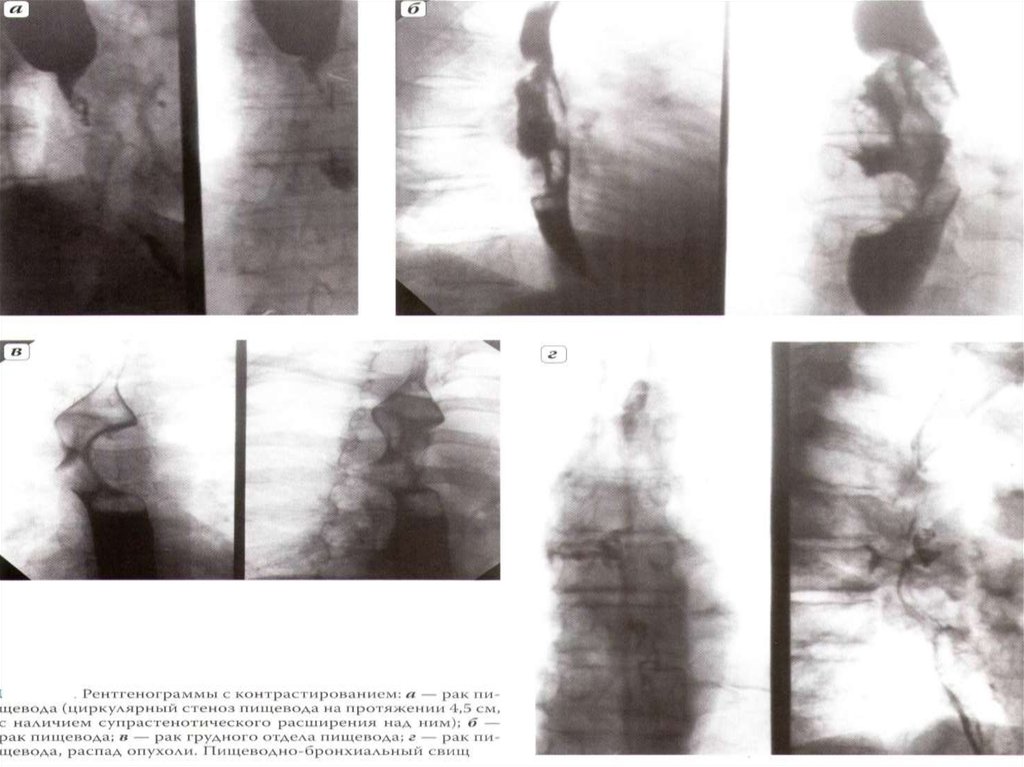

8.

Схема изменений при

раке пищевода –

органический стеноз

кардиоспазме –

патологический спазм

9.

1

2

3

1-дефект наполнения, 2- дилятация и сужение просвета

пищевода, 3 - изьеденность внутреннего контура.

10.

11.